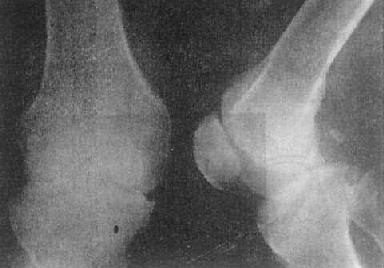

图2-1-14 关节破坏——膝关节结核

膝关节关节间隙变窄,关节面边缘有虫蚀状骨破坏